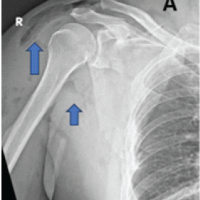

A 26-year-old male presented after a high-velocity road traffic accident with isolated left hip trauma. He was hemodynamically stable with no associated head, thoracoabdominal, or spinal injuries. The left lower limb appeared shortened and internally rotated, with severe hip pain and restricted active and passive motion. Distal pulses were palpable, and sensory and motor examination of the sciatic and femoral nerve distributions was normal. Anteroposterior pelvic radiographs (Fig. 1) and Judet views showed disruption of both the iliopectineal and ilioischial lines, indicating involvement of the anterior and posterior columns, with preservation of the obturator foramen, consistent with a both-column pattern. Computed tomography (CT) with three-dimensional reconstruction confirmed an anterior column posterior hemi-transverse acetabular fracture involving the weight-bearing dome and posterior wall (Fig. 2) according to the Letournel classification.

Figure 1: Anteroposterior radiograph of the pelvis at presentation showing disruption of the iliopectineal and ilioischial lines consistent with a both-column acetabular fracture, with the femur head subluxation.